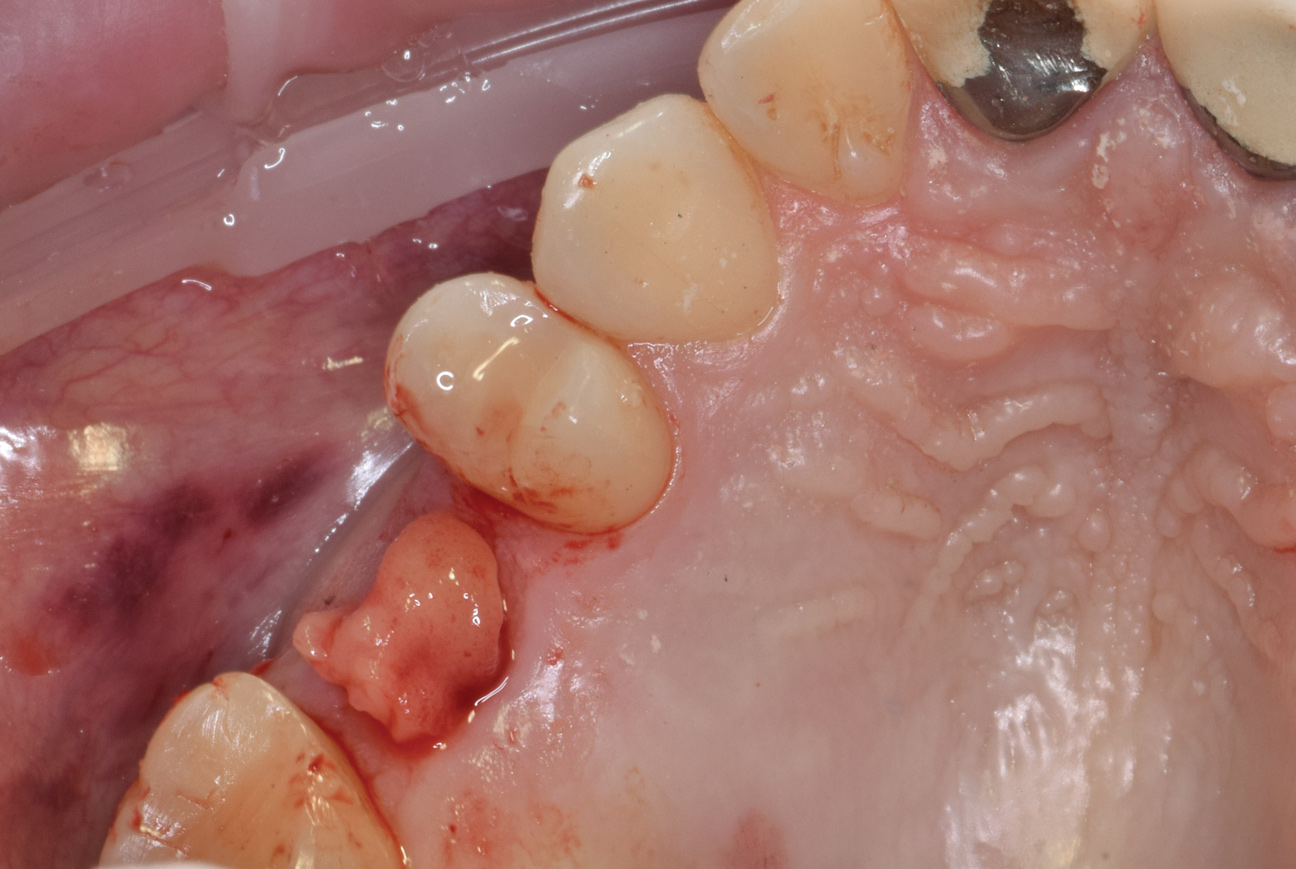

When the patient returned for treatment, anesthesia was administered in local infiltrations around the molar that would be extracted. The affected molar was atraumatically extracted and the socket (ie, type 1 Salama classification) was thoroughly curetted to remove any granulation tissue and debris related to the failed endodontic treatment.

The prepared extraction socket was filled with the graft mixture and covered with a resorbable collagen membrane. A figure eight suture using a 6-0 polypropylene blue monofilament was placed to retain the membrane and socket graft during the initial days of healing. When the patient returned a week later and the suture was removed, the site demonstrated minimal inflammation and partial closure of the gingiva was observed.

(1.) Radiograph of the missing maxillary molar and available bone between the crest and maxillary sinus.

Figure 1